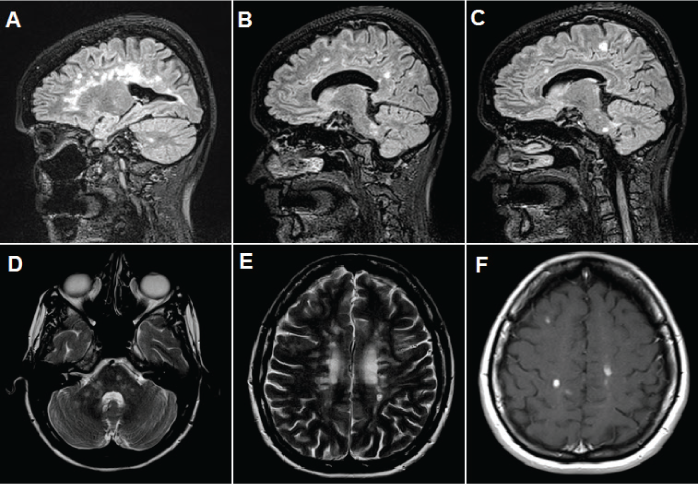

An RBD was considered, and a polysomnographic recording that was performed at another institution confirmed this diagnosis by showing electromyographic activity with excessive twitching observed in the tibialis anterior muscle and the flexor muscles of the hand in rapid eye movement (REM) sleep. However, no reported movements were seen during REM sleep. Other sleep disorders, such as parasomnias and obstructive sleep apnea (her reported apnea-hypopnea index was 1.4 per hour of sleep), were ruled out. She had normal levels of thyrotropin and vitamin B12; results of antinuclear antibody, anti–double-stranded DNA, Venereal Disease Research Laboratory, human T-lymphotropic virus type 1, and human immunodeficiency virus testing were negative. Brain magnetic resonance imaging was performed (Figure 1) and revealed multiple perpendicular demyelinating lesions in the corpus callosum and the periventricular and juxtacortical regions. There were also lesions in the pons, bilateral cerebellar peduncles, and hemispheres. There was contrast enhancement of punctiform lesions in the bilateral frontoparietal regions and right inferior cerebellar peduncle and some in the periventricular region.

Brain magnetic resonance images